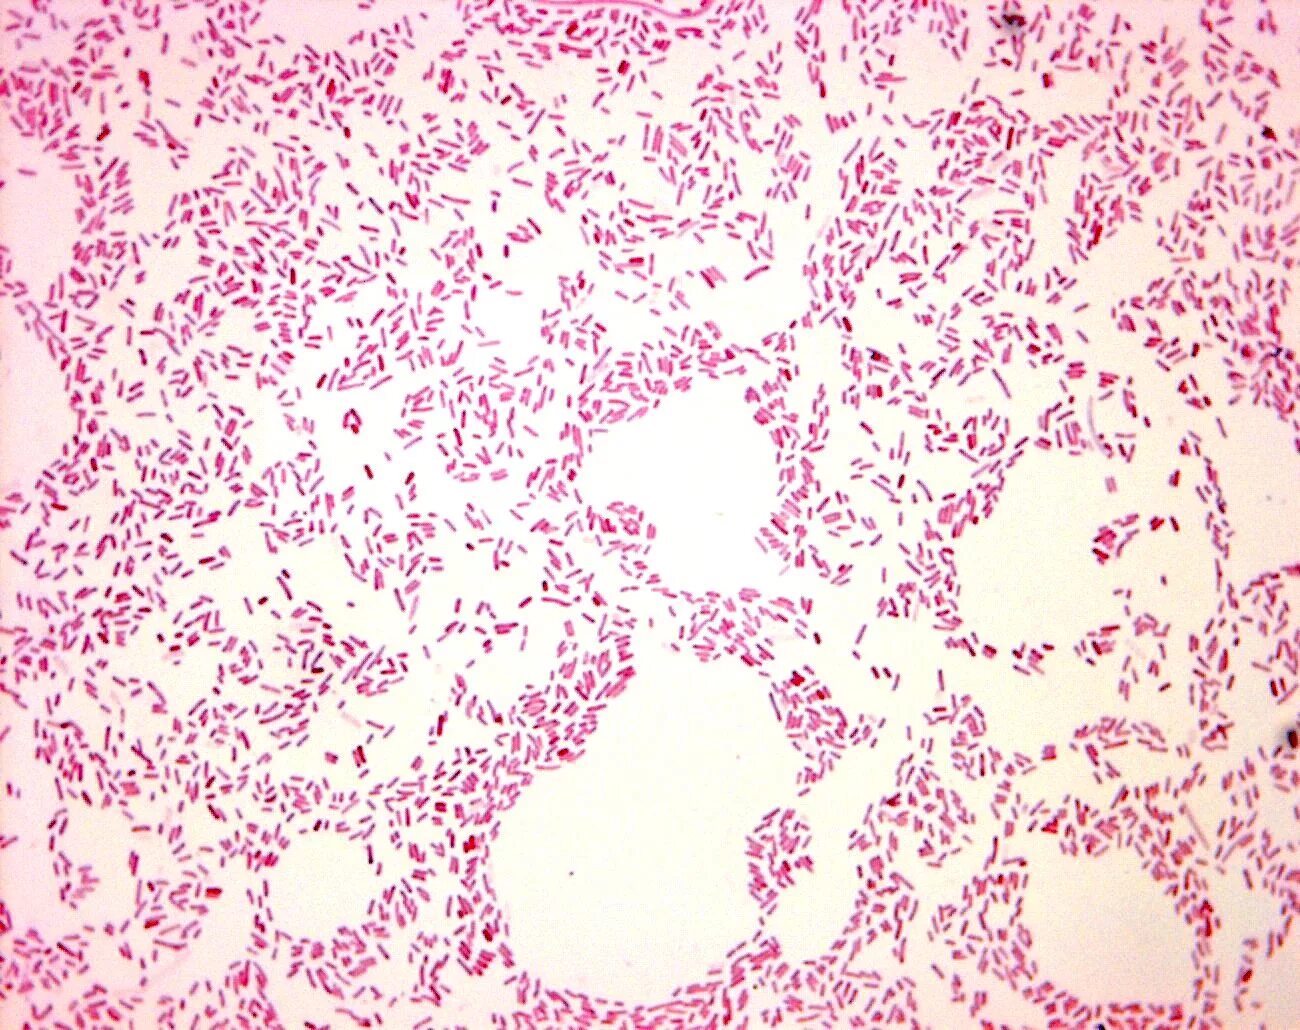

Микроскопия окрашенных